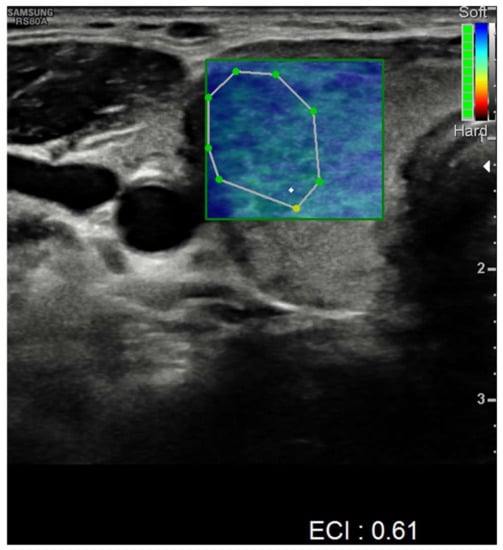

| Ultrasound findings at presentation | Asymmetric thyroid enlargement with two hypoechoic areas with no internal vascularity on right thyroid lobe | Diffuse thyroid enlargement with hypoechoic areas with heterogeneous echotexture and no evidence of increased vascularity | Diffuse enlargement of thyroid gland with hypoechoic nodules with hyperechoic shoots (micronodular pattern) without increase in vascularity | ||||||||||||||

| Ultrasonographic findings | ||||

| Hypoechoic areas | 8 (80%) | 3 (75%) | 5 (83.3%) | 1 |

| Heterogeneous echotexture | 4 (40%) | 1 (25%) | 3 (50%) | 0.571 |

| Reduced blood flow at Doppler-US | 6 (60%) | 1 (25%) | 5 (83.3%) | 0.119 |